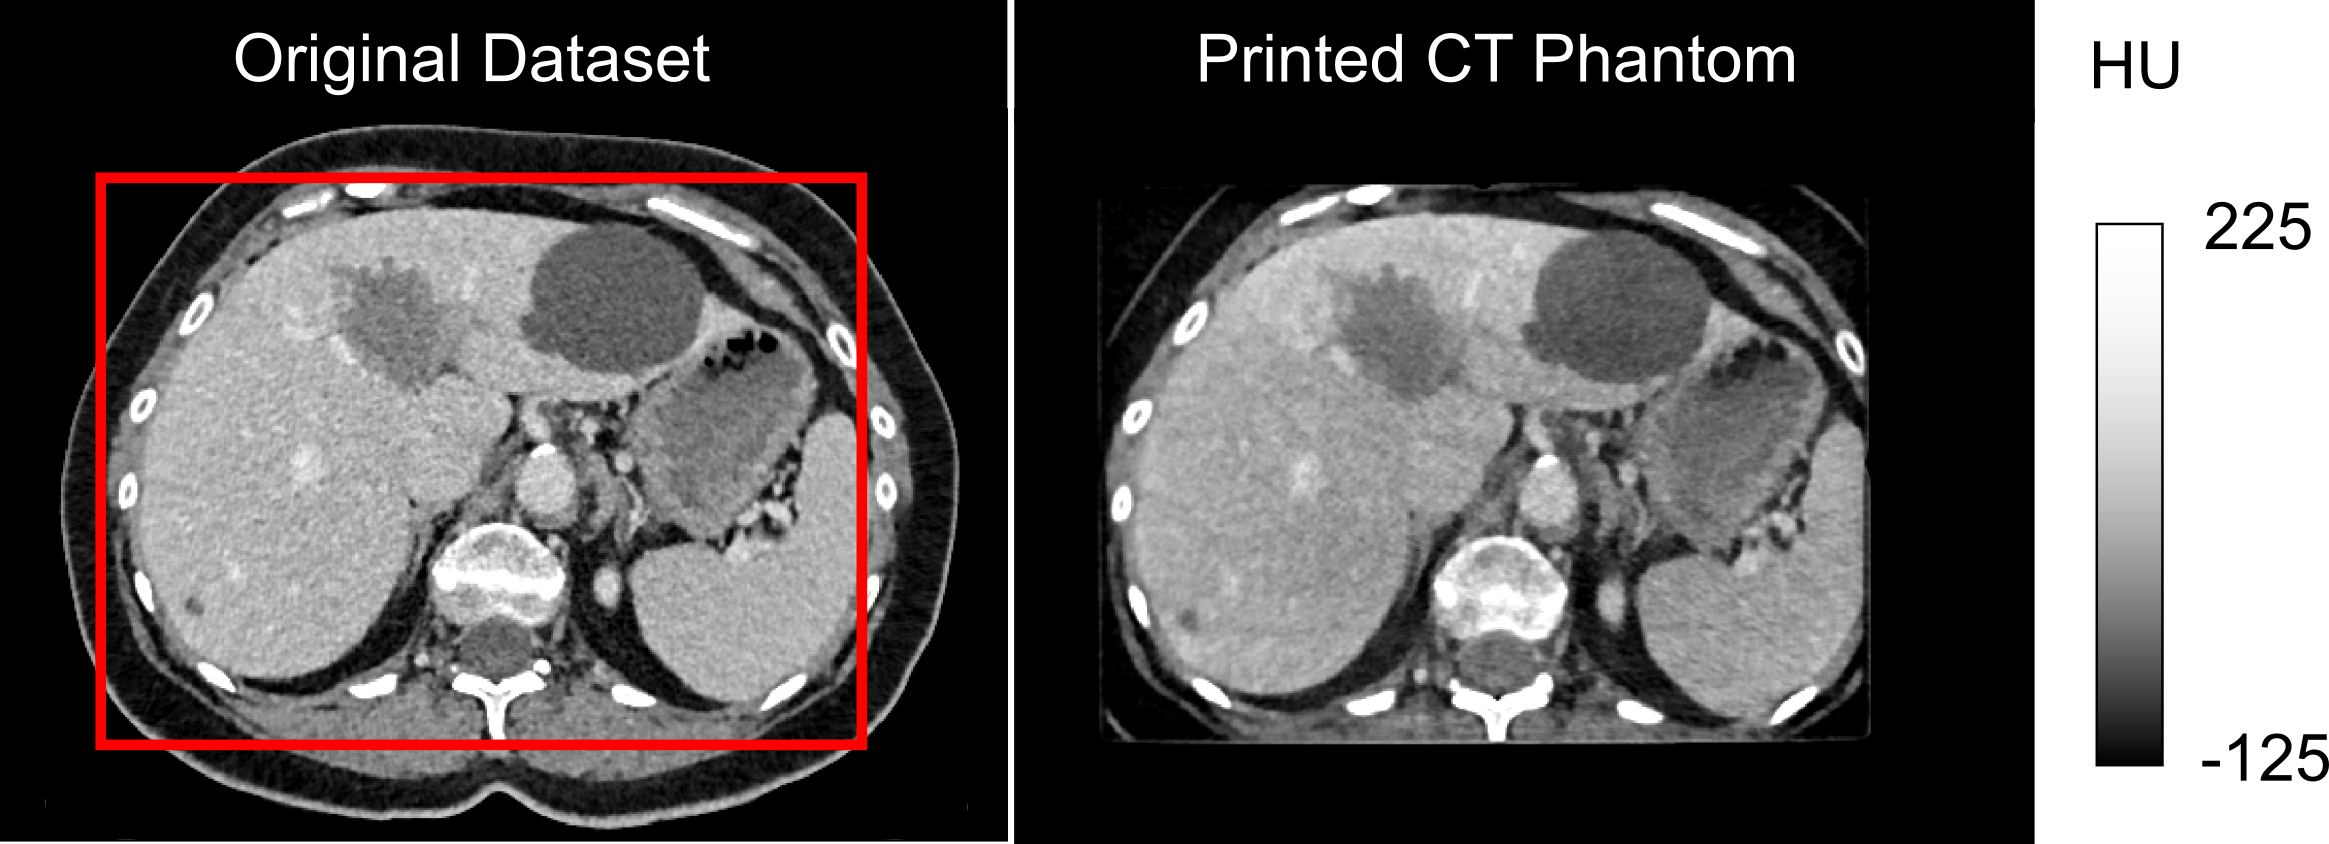

Pipeline for automatic evaluation of image data sets

The acquired data sets were processed according to the flowchart shown in figure 2. After measuring the phantom in the CT scanner, the data was first pseudonymized and then uploaded to the Kheops platform. From here, further processing could take place. In our project, the ROIs once defined in the phantom were now registered to each newly acquired dataset. Image features (radiomics) were then extracted. The pipeline can be used in general for image feature extraction as long as a dataset and the corresponding ROIs are available. The pipeline is provided as open source.

Figure 2: Image analysis pipeline and related SPHN QA4IQI outcomes.